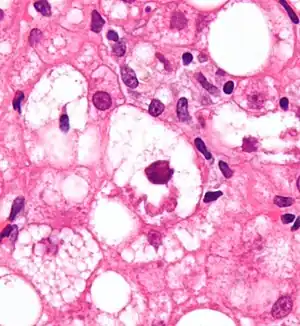

| Micrograph showing a Mallory body, a histopathologic finding associated with alcoholic hepatitis. H&E stain. | |